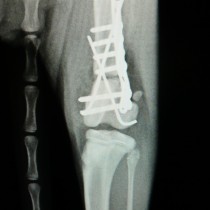

新しい医療機器(整形外科ドリル)を導入しました。